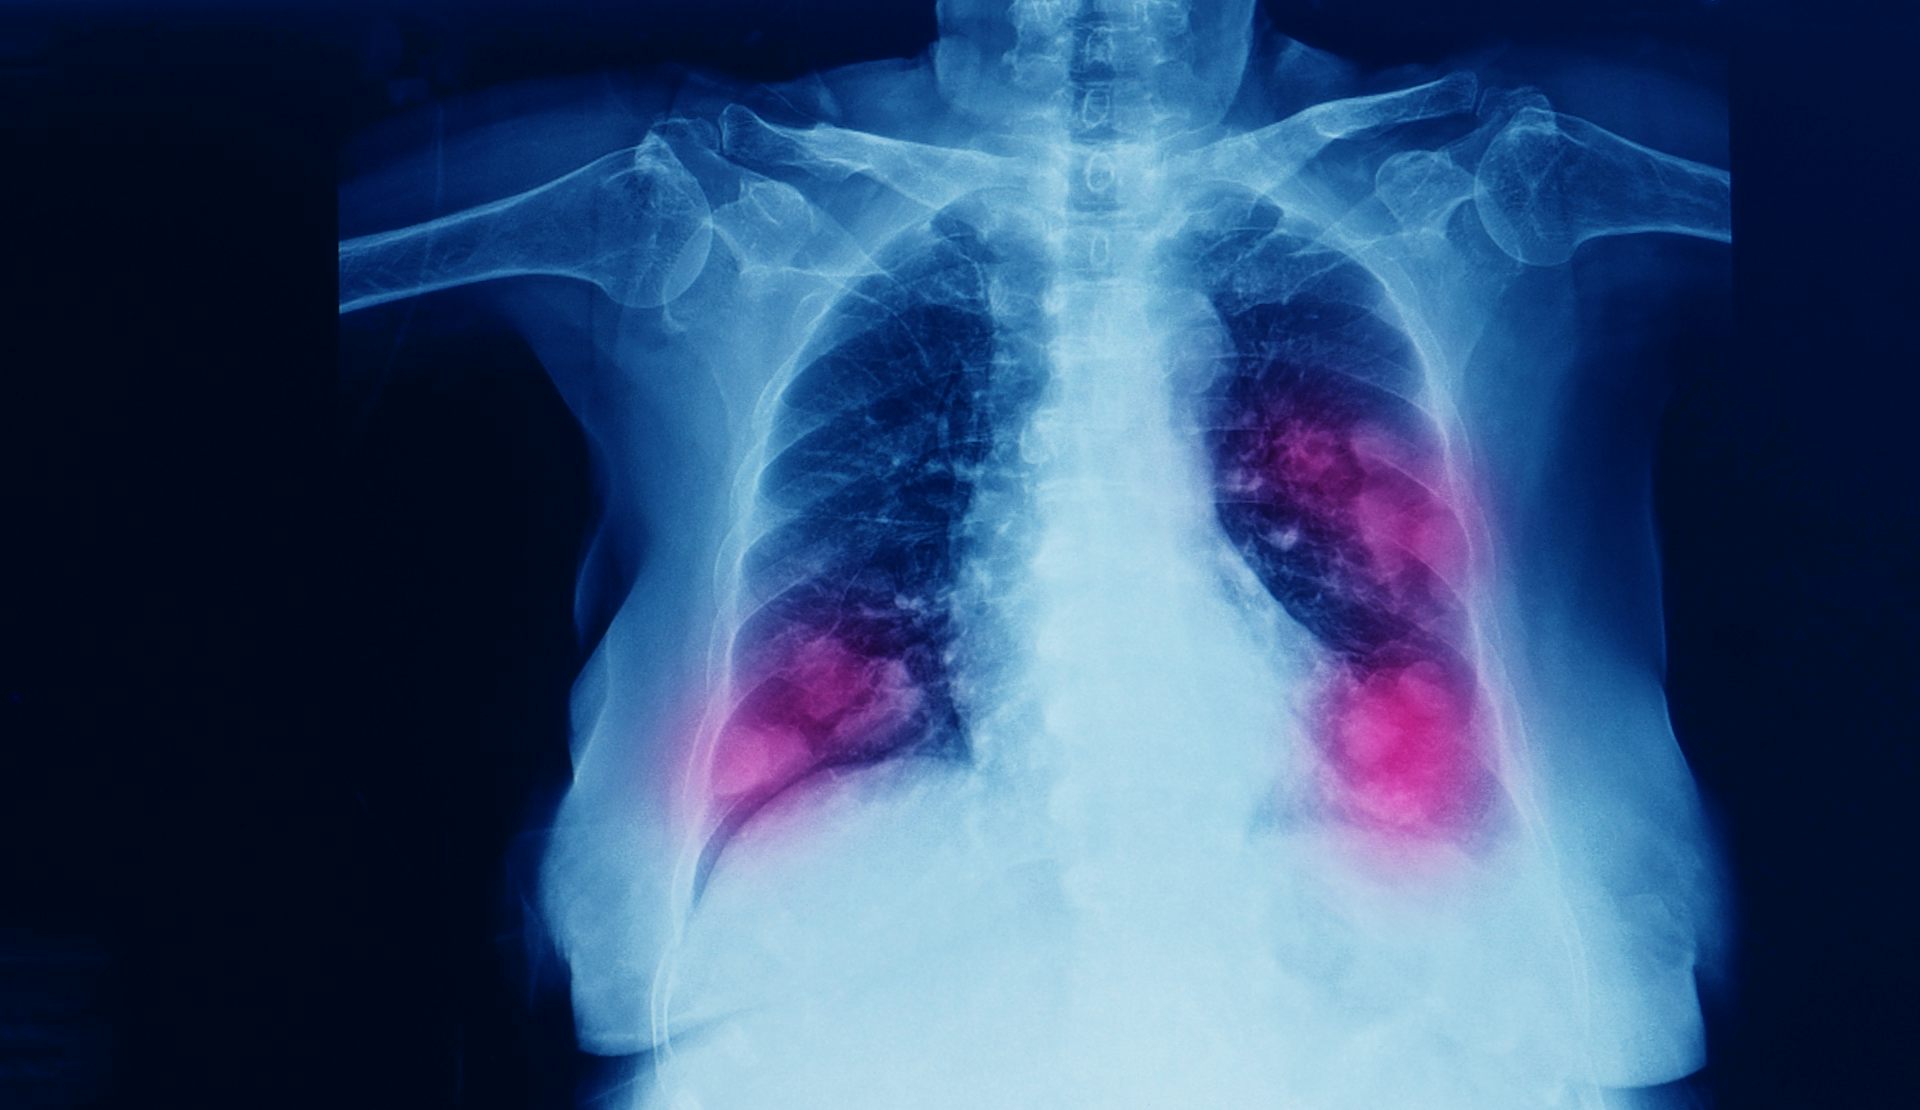

La edición genética podría desactivar al principal culpable del cáncer de pulmón

Durante años, el gen KRAS, cuya mutación es el principal causante de la expansión del cáncer de pulmón, había resistido todos los intentos de bloquearlo con fármacos contribuyendo a que este tipo de cáncer fuera el más extendido en el mundo. Pero ahora han surgido dos vías para atacarlo y una de ellas se basa en la técnica CRISPR de edición genética que permite eliminar la mutación del gen de raíz. En The Conversation detallan en qué consiste esta técnica que abre un camino distinto a la oncología y podría convertirse en la terapia del futuro.

El paso del tiempo lo cambia casi todo menos la principal causa de cáncer en el mundo, que en las últimas décadas ha sido el cáncer de pulmón. Solo en España se diagnostican más de 30 000 casos cada año, y la supervivencia a cinco años apenas alcanza el 20 %. Parte del problema es que los tumores suelen detectarse tarde y que los tratamientos, incluso los más novedosos, acaban perdiendo eficacia.